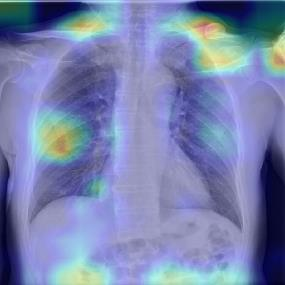

Chest X-ray (CXR) is the most typical diagnostic X-ray examination for screening various thoracic diseases. Automatically localizing lesions from CXR is promising for alleviating radiologists' reading burden. However, CXR datasets are often with massive image-level annotations and scarce lesion-level annotations, and more often, without annotations. Thus far, unifying different supervision granularities to develop thoracic disease detection algorithms has not been comprehensively addressed. In this paper, we present OXnet, the first deep omni-supervised thoracic disease detection network to our best knowledge that uses as much available supervision as possible for CXR diagnosis. We first introduce supervised learning via a one-stage detection model. Then, we inject a global classification head to the detection model and propose dual attention alignment to guide the global gradient to the local detection branch, which enables learning lesion detection from image-level annotations. We also impose intra-class compactness and inter-class separability with global prototype alignment to further enhance the global information learning. Moreover, we leverage a soft focal loss to distill the soft pseudo-labels of unlabeled data generated by a teacher model. Extensive experiments on a large-scale chest X-ray dataset show the proposed OXnet outperforms competitive methods with significant margins. Further, we investigate omni-supervision under various annotation granularities and corroborate OXnet is a promising choice to mitigate the plight of annotation shortage for medical image diagnosis.